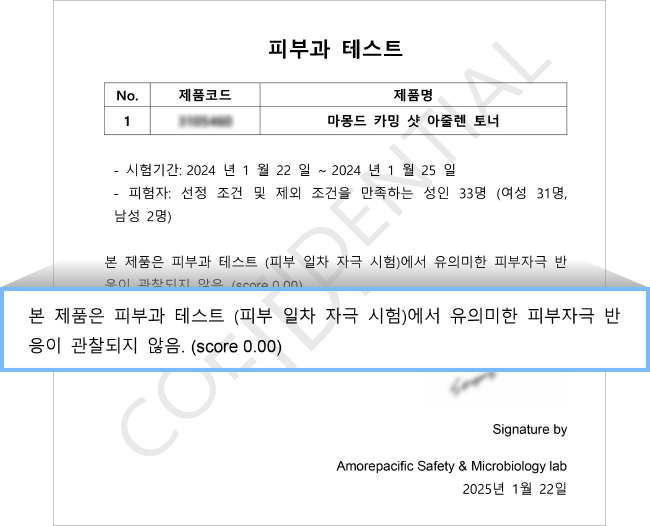

피부 진정 케어를 위한

자극지수 0.00

& 미산성 pH 포뮬러

자극 부담 없이

매일 매일 편안하게 사용하도록

피부 자극 지수 0.00 확인

피부과 테스트

제품명: 마몽드 카밍 샷 아줄렌 토너

- 시험기간: 2024년 1월 22일 ~ 2024년 1월 25일

- 피험자: 선정 조건 및 제외 조건을 만족하는 성인 33명 (여성 31명, 남성 2명)

본 제품은 피부과 테스트 (피부 일차 자극 시험)에서 유의미한 피부자극 반응이 관찰되지 않음. (score 0.00)

Amorepacific Safety & Microbiology lab.

2025년 1월 22일